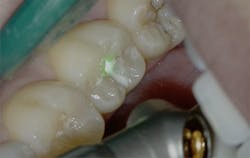

Figure 1: 9.3-micron CO2 laser (Solea, Convergent Dental)

Figure 2: Class I pre-op lesion. Photo courtesy of Jeff Rhode, DDS.

Figure 3: Class I cavity prep after laser. Photo courtesy of Jeff Rhode, DDS.